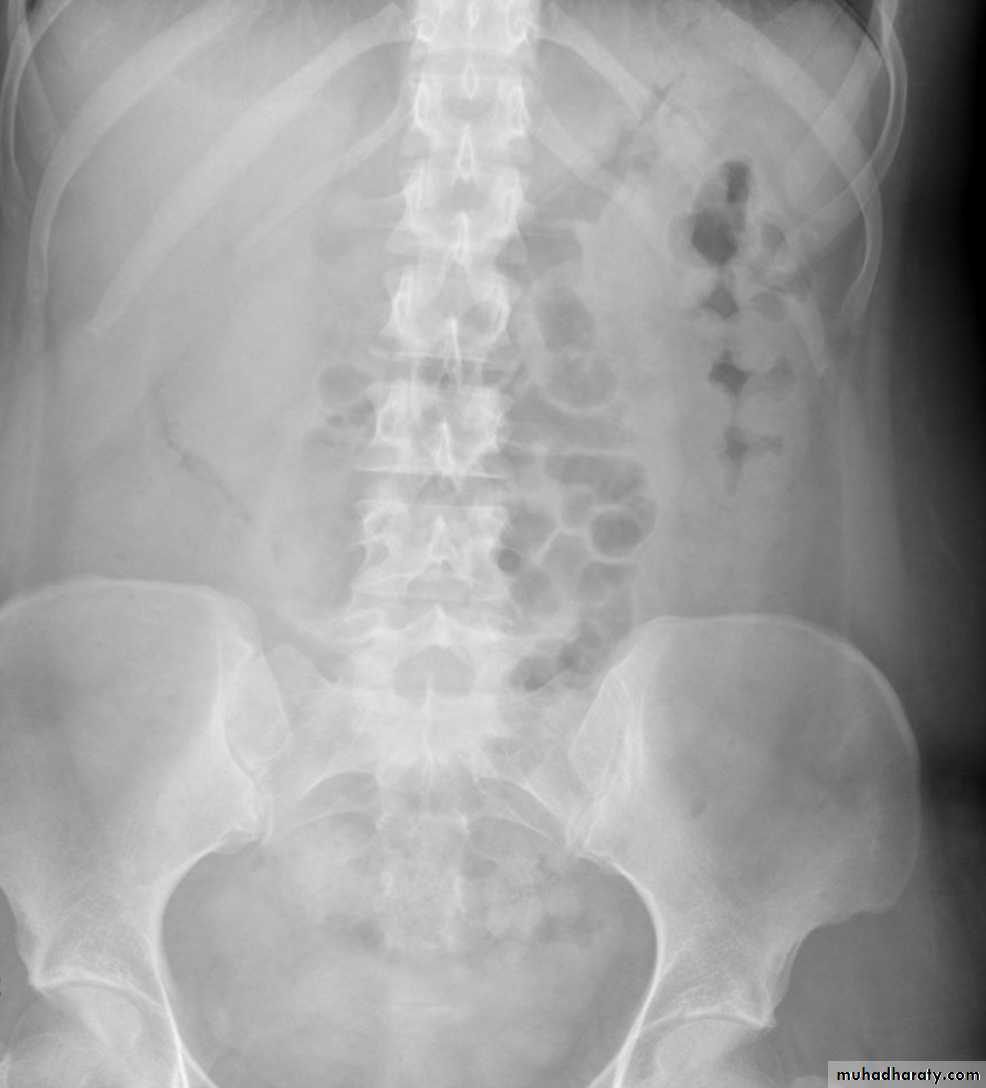

Large versus small bowel on AXR

Large bowel Small bowel

Large bowelperipheral

haustra

Small bowel

central

valvulae conniventes

Valvulae conniventes:

mucosal folds thatgo right across small bowel

peripheral

haustra± faeces

larger calibre (>5cm<9cm)

no faeces

smaller calibre

(2-2.5cm)